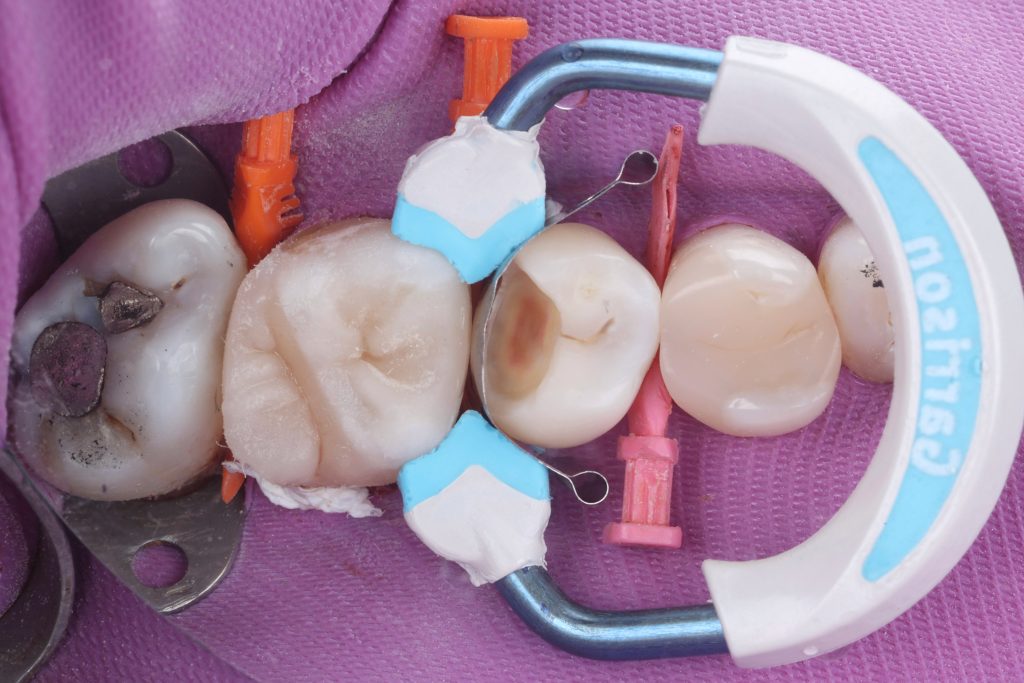

started with first molar , matrix system was applied. The marginal seal was checked.

separation ring was applied distally to compensate for the matrix thickness and create a precise contact. Size & height of matrix is very important step.

Let’s start with proximal walls by snow-blow technique ( small amounts of flowable composite followed by packing of packable composite)

Very important step here to make the height of marginal ridge the same or slightly higher than the marginal ridge of adjacent tooth, to avoid any high spots.